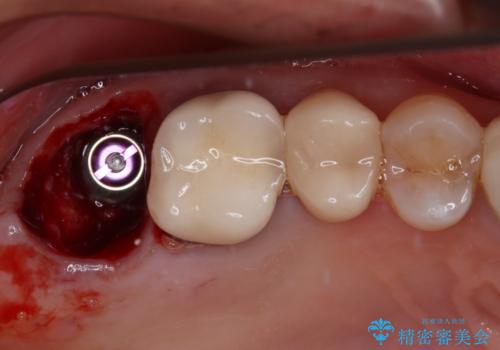

仮歯に置き換えた際に歯周外科処置を行い、歯肉の腫脹が落ち着いたことを確認してオールセラミッククラウンにて補綴することとしました。

外科処置後の痛みを気にしていましたが、小規模の処置であったため、痛みを感じることはほとんどありませんでした。

気になっていた腫脹がなくなり、患者様には大変満足していただきました。